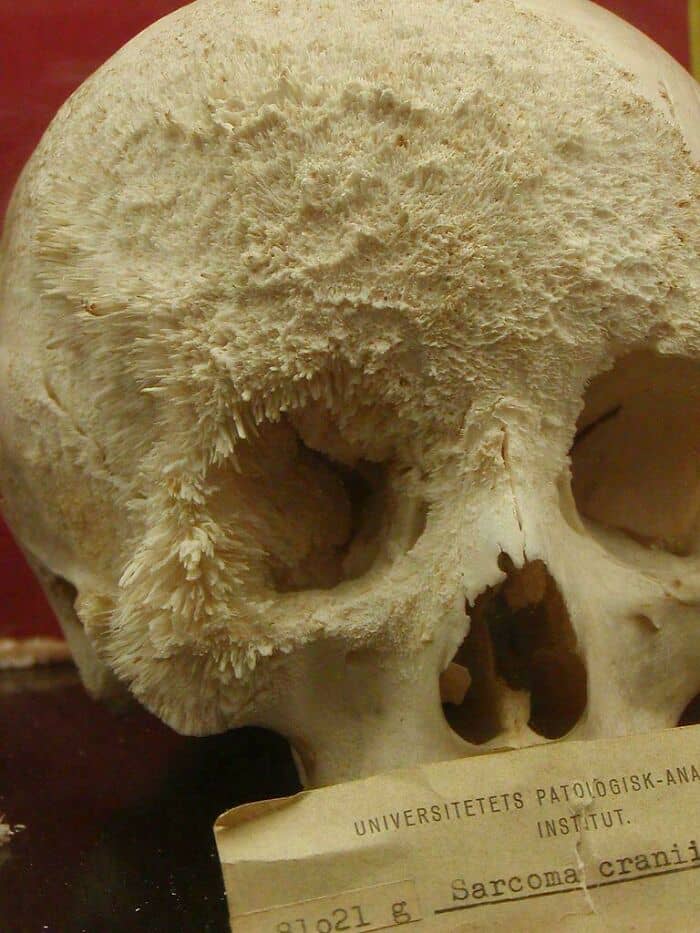

#19 Thanks, I Hate Bone Cancer